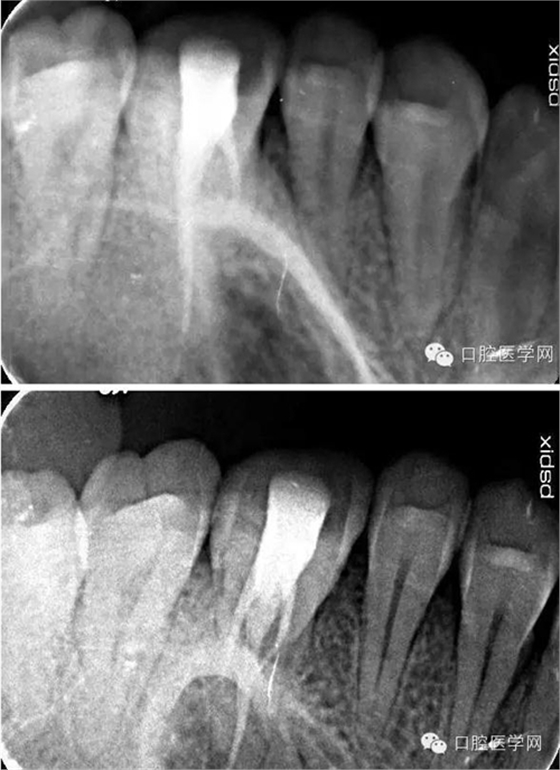

術(shù)后x線片: